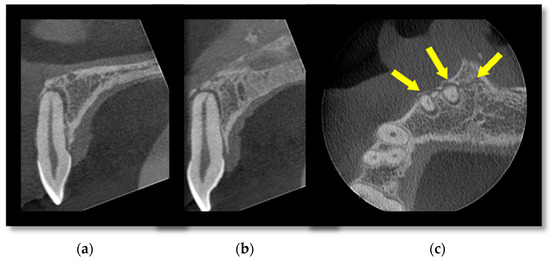

3.1. Cone Beam CT for Assessment of Dentoalveolar Fractures

- Long, H.; Zhou, Y.; Ye, N.; Liao, L.; Jian, F.; Wang, Y.; Lai, W. Diagnostic accuracy of CBCT for tooth fractures: A meta-analysis. J. Dent. 2014, 42, 240–248. [Google Scholar] [CrossRef] [PubMed]

- Sha, X.; Jin, L.; Han, J.; Li, Y.; Zhang, L.; Qi, S. Comparison between periapical radiography and cone beam computed tomography for the diagnosis of anterior maxillary trauma in children and adolescents. Dent. Traumatol. 2022, 38, 62–70. [Google Scholar] [CrossRef] [PubMed]

- Bernardes, R.A.; de Moraes, I.G.; Duarte, M.A.H.; Azevedo, B.C.; de Azevedo, J.R.; Bramante, C.M. Use of cone-beam volumetric tomography in the diagnosis of root fractures. Oral Surg. Oral Med. Oral Pathol. Oral Radiol. Endodontol. 2009, 108, 270–277. [Google Scholar] [CrossRef]

- Chavda, R.; Mannocci, F.; Andiappan, M.; Patel, S. Comparing the in vivo diagnostic accuracy of digital periapical radiography with cone-beam computed tomography for the detection of vertical root fracture. J. Endod. 2014, 40, 1524–1529. [Google Scholar] [CrossRef] [PubMed]